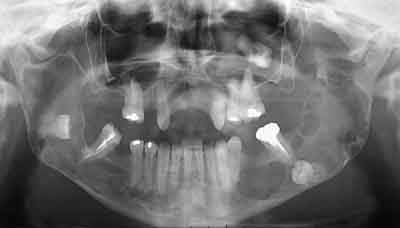

Femme de 40 ans. Aucun antécédent (notamment chirurgical) en dehors d'un DNID, d'un tabagisme modéré (5 paquets-année) et d'une surcharge pondérale. Consulte pour apparition progressive d'une volumineuse voussure dans les 2 vestibles inférieurs et d'une modification consécutive de la forme de la partie inférieure de son visage. A l'examen clinique : tuméfaction dure et fixée dans les 2 vestibules. Sensibilité (V3) normale. Gencive normale. Dents restantes non mobiles, vitales. Pas d'adénopathies palpables. Biologie non faite pour l'instant. Je vous joinds l'OTP et le scan. Diagnostic et options de traitement?

du coté de la dent incluse dans le ramus, on peut penser comme diagnostic probable a un kyste d'origine dentaire -image uniloculaire bordée sur son pourtour par une corticale bien individualisée et sur le scanner disparition de l'espace péricoronaire de la couronne avec continuité de toute la cavité.

on a le choix entre pas mal de choses dont l'ameloblastome, le kyste multiloculaire, le kyste dentigère, la tumeur de Pindborg

je ne pense pas a l'ameloblastome, on n'a pas ici l'image caracteristique en "bulles de savon",on n'a pas de projection de petites cavités radioclaires en périphérie et pas de resorption des dents adjacentes qui restent vitales

le kyste multiloculaire montre plusieurs compartiments bien définis , ici l'origine dentaire est possible mais n'explique pas les images multiples derriere la molaire donc peu probable

on peut penser a une tumeur de Pindborg, les pourtours des cavités sont moins nettes et rondes que pour un améloblastome et de plus la tumeur a des bords irréguliers et une tendance à l'envahissement local qui semble confirmé par la disparition de la corticale supérieure sur la partie coronaire de la mandibule

Bref, en ce qui concerne ce cas (assez récent), je vous livre le raisonnement qui a été le notre : probables kystes péricoronnaires sur les dents incluses (il n'y a pas de dents "surnuméraires"...). Décision d'abord chirurgical pour énucléation des 3 kystes (les ponctions ne "marchent" pas dans ces lésions) et examens anatomopathologiques extemporanés pour décider, en per-opératoire, de la conduite à tenir (photo 1).

Diagnotic extemporané : kératokystes (!). Les dents incluses se sont donc avérées être un piège diagnostic! Le traitement s'est de ce fait contenté d'un curetage appuyé des paroies osseuses, conservation des 2 nerfs dentaires et, en raison de la taille des kystes mandibulaires et du risque de fracture post-opératoire, nous avons y avons associé une greffe (hydroxyapatite + os autologue (crête illiaque) + PRP) au niveau mandibulaire uniquement (photos 2 et 3)et blocage intremaxillaire pendant 15 jours.